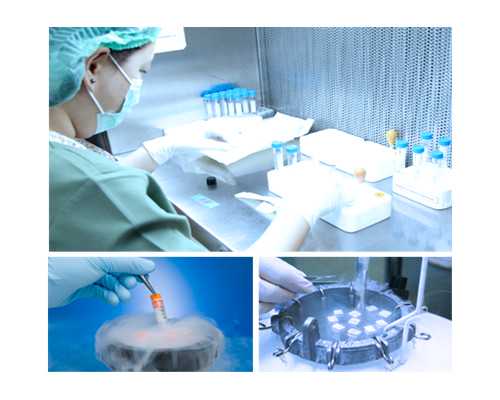

試管嬰兒技術(shù)一般是指體外受精技術(shù),是在實驗室條件下進行的一種技術(shù),其特點是在實驗室條件下將精子和卵子放在一起,使精子和卵子進行結(jié)合,達到受精的目的。試管嬰兒技術(shù)進入周期后,具體能做多久取決于女性的月經(jīng)周期。正常情況下,月經(jīng)周期為 28-32 天,受精的最佳時間通常是月經(jīng)周期的第 11-14 天,也就是排卵期。

檢查是試管嬰兒周期的重要組成部分。為了最大限度地提高試管嬰兒的成功率,夫妻雙方都應(yīng)為檢查做好準備,以確保受精的準確性。